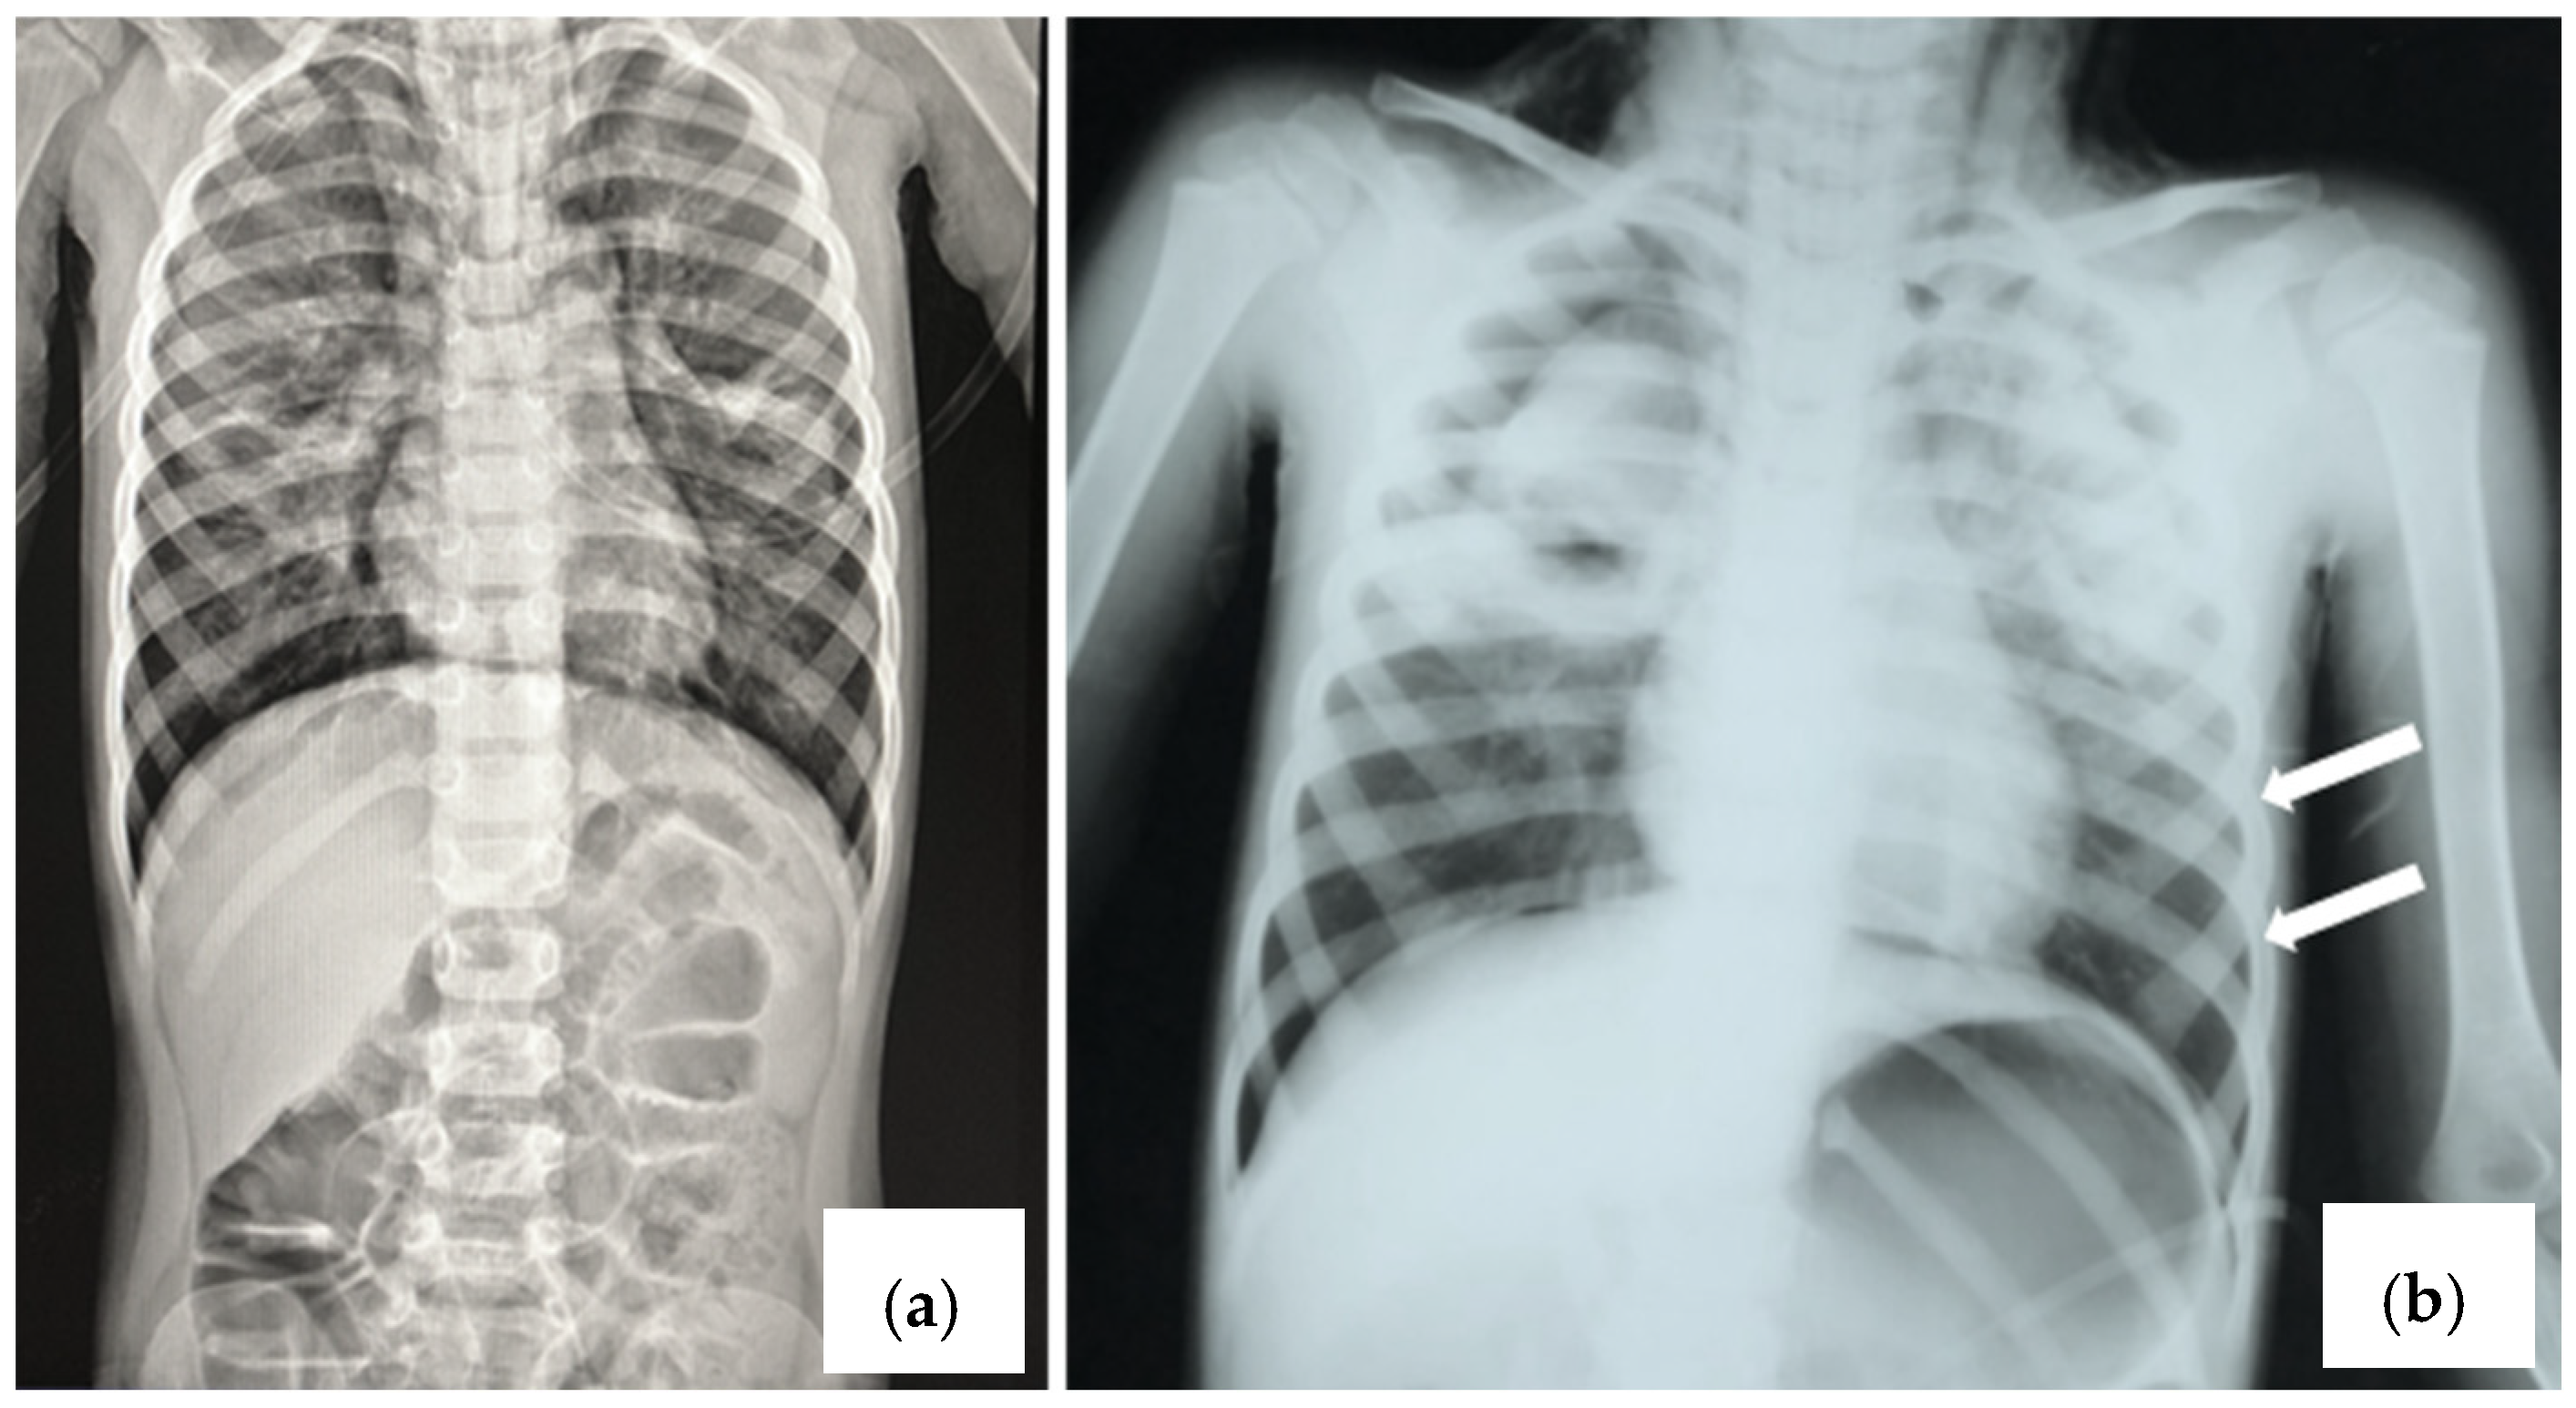

2.1. Case 1

2.2. Case 2